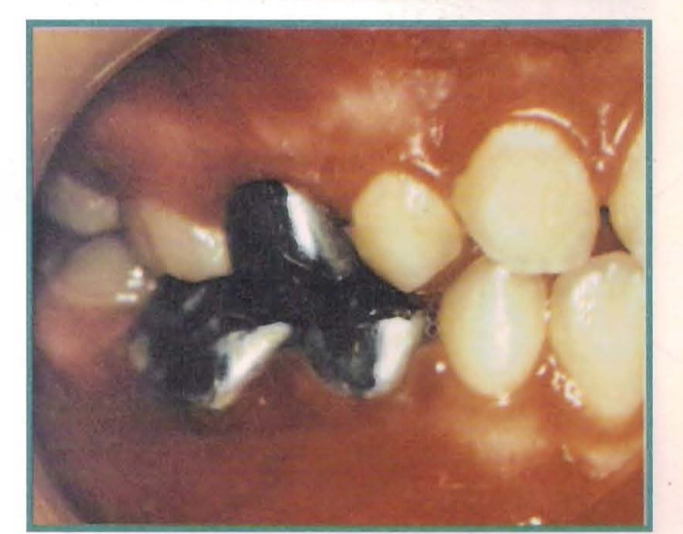

Paciente: Johatia Tapia

Sexo: Feminino

Idade: 4 anos e 9 meses

Apresenta-se à consulta encaminhada pelo Odontopediatra, que ao ver a gravidade do quadro demanda a consulta e eventualmente o tratamento, mesmo com a pouca idade da menina. A análise clínica pouco nos disse sobre a etipatogenia do caso, embora haja dois dados a mencionar: o ponto subnasal mole não aparece afundado no perfil e observa-se papada, produto de uma atitude postural baixa da língua.

Ao observar os arcos, vemos uma mordida invertida anterior e relações sagitais de mesiorrelação, observando-se também classe III na chave canina e molar.

É ao fazer o estudo cefalométrico que encontramos as alterações que configuraram essa síndrome. Como se observa, a posição do maxilar superior em relação à base do crânio é praticamente normal, e o tamanho do maxilar superior supera o esperado. É o tamanho da mandíbula, com 4 mm de excesso sobre o esperado, onde está a resposta que buscamos.

Nos encontramos então frente a uma mesiorrelação por aumento de tamanho da mandíbula.

Felizmente, a paciente tem algo menos de cinco anos, e nos dedicamos a resolver o caso apelando à remodelação das alveolares. Instala-se um Blimmer C.

Após um ano, faz-se outra avaliação cefalométrica, onde se observa que a mandíbula continuou crescendo, talvez sobre padrões genéticos.

Não obstante o que foi dito, a clínica mostra um harmonioso equilíbrio morfofuncional.